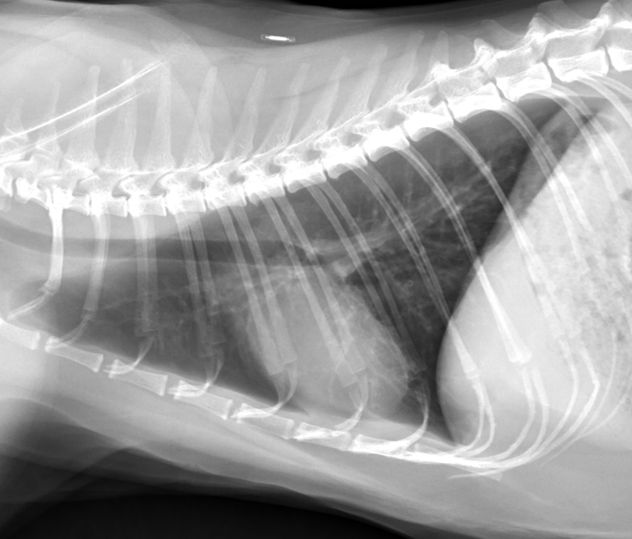

Crise D Asthme Chien. L'asthme chez le chien causes, symptômes et traitement Concrètement, cela signifie que le système immunitaire considère ces. Causes de l'asthme bronchique L'asthme bronchique survient lorsque les bronches du chien sont obstruées par des matières muqueuses, qu'elles se mettent à spasmer et à rétrécir les voies respiratoires

Votre chien fait de l'asthme ? Il est essoufflé, il tousse, sa respiration est sifflante? Comment l'éviter et le soigner. Les chiens obèses et les chiens brachycéphales sont plus sensibles à cette pathologie. Qu'il s'agisse d'une maladie permanente, chronique ou allergique, les crises d'asthme sont très gênantes.

L'asthme chez le chien causes, symptômes et traitement. Des difficultés respiratoires s'installent, devenant très handicapantes dans sa vie de tous les jours Bien qu'il existe plusieurs facteurs déclencheurs susceptibles d.

Asthme les chiens réduisent les symptômes chez les enfants Chien, Asthme, Asthme enfant. Même si avoir un chien asthmatique à la maison est plus rare qu'avoir un chat asthmatique, il est toujours possible que votre meilleur ami soit atteint par cette maladie respiratoire, surtout s'il fait partie des petites races de chien s Parce que dans certains cas, les crises d'asthme du chien sont fatales, il est très important de trouver un traitement approprié, afin de sauver la vie de votre chien